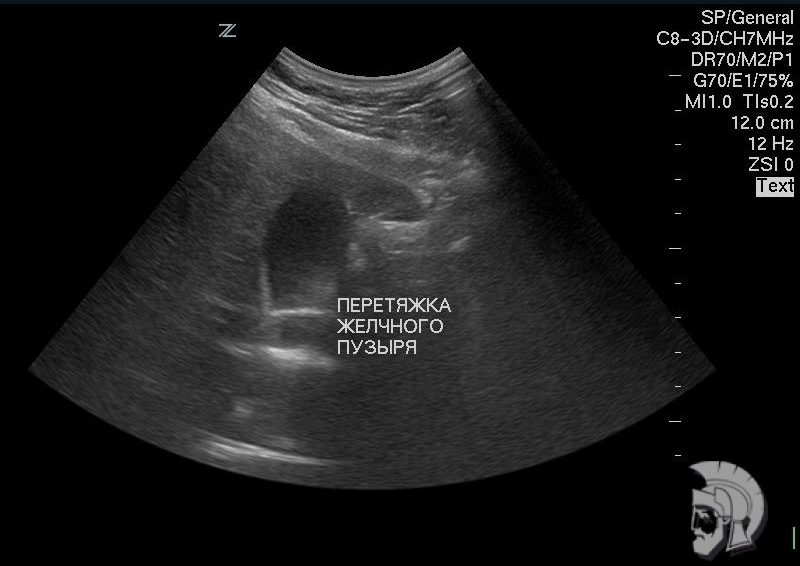

| Фото желчного пузыря. Желчный пузырь с перетяжкой у мужчины 48 лет |